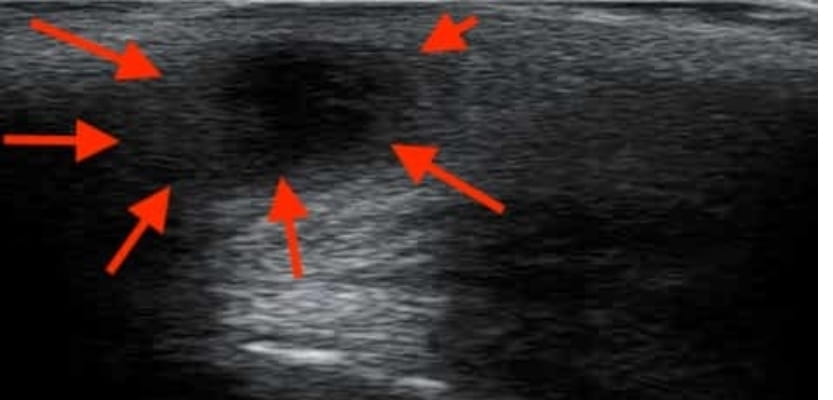

L’imagerie (échographie ou IRM périnéale) est réservée aux formes complexes ou atypiques, notamment lorsqu’un doute existe avec une fistule anale ou une hidradénite suppurée (maladie de Verneuil). Ces deux pathologies peuvent mimer un kyste pilonidal mais nécessitent un traitement différent. En cas de doute, l’avis d’un chirurgien colorectal ou d’un proctologue est recommandé.